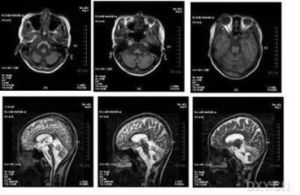

小腦萎縮小腦萎縮核磁共振成像(MRI)檢查:掃瞄腦部,可以見到病變進行中的小腦萎縮。